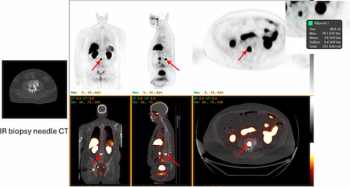

For patients with gastric cancer, (68Ga)Ga-FAPI-04 PET offered double the sensitivity for lymph node metastases in comparison to (18F)FDG PET.

For patients at high-risk for biochemical recurrence of prostate cancer, PSMA PET/CT findings revealed that 77 percent had one or more prostate lesions after undergoing local radiation therapy or radical prostatectomy, according to a recent study.